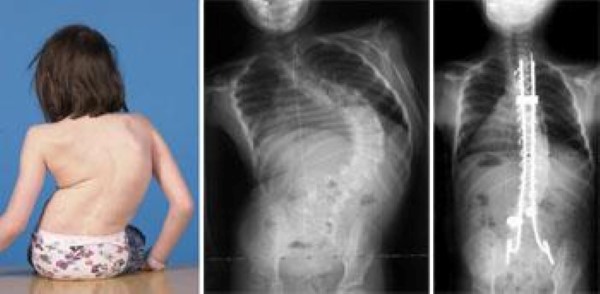

spinal fusion for child with myelomeningcele and scoliosis

An eight-year-old girl with a 100° scoliosis curve. X-rays show the curve before and after spinal fusion surgery.

Courtesy of Texas Scottish Rite Hospital for Children